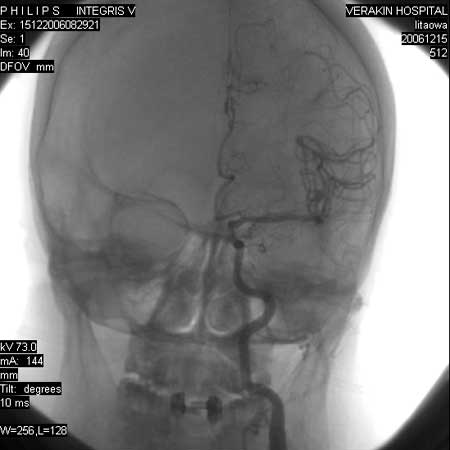

标题: DSA0063:颈内动脉血管造影

女,60岁,行全脑血管造影,图片较多,选了左颈内动脉造影100幅图中的10幅图片,请包涵。

更正:今天才看到本例脑血管造影全部过程,实际上仍是单侧的颈内动脉造影,只是在造影过程中,导管头位置平c4水平,刚好越过颈外动脉,本帖图片中颈外动脉显影系高压注射时造影剂部分返流到颈外动脉所致,特此更正!

另外:大家讨论的\"动脉瘤\"实际是血管分支重叠影像,本帖单侧颈内动脉仅见轻度动脉硬化性狭窄..参考旋转dsa请连接:http://www.sdhct.com.cn/radinet/read.php?tid=19818

旋转dsa在脑血管检查中,是对常规正侧位dsa检查的重要补充,很好地应用该技术可以提高检出率,在使用中注意技术参数的设定,诸如流率、给药量、旋转速度、旋转起始点的设置度、旋转角度的大小与病变血管团的大小有关,旋转的起始位置及方向,是保证病变血管支充分显示的关键。它主要是参考正侧位dsa图像,观察供血支是否显示及走向,如果在正位或侧位上部分显示,在相应的侧位或正位上不显示,旋转起始位置应为供血支不显示的正位或侧位。如果都不显示,起始位置为正位或侧位皆可,造影剂的注射参数的设定,主要注意造影剂充盈时间与旋转角度需相匹配,一般设定低流速使之旋转全程中均有造影剂灌注。

虽然应用了旋转dsa检查技术,但仍有部分蛛网膜下腔出血的患者,检查结果为阴性,分析原因可能为:(1)病因不是动脉瘤,有些高血压动脉硬化或血管畸形的患者,亦可引发蛛网膜下腔出血;(2)出血血管处于痉挛状态,使造影剂不能充分灌注使之充盈显影;(3)小血管动脉瘤被血栓充填,这时表现为正常血管影像。